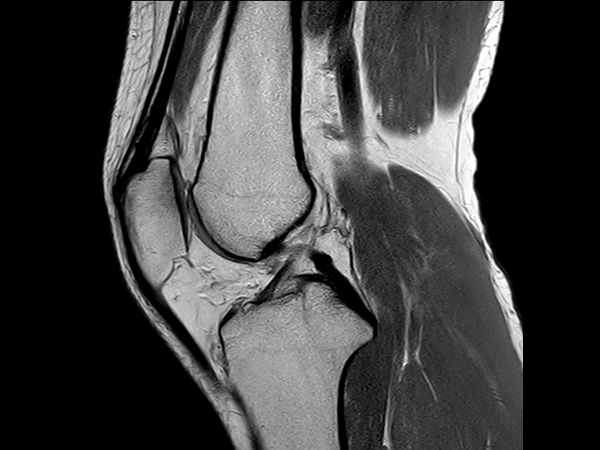

Sagittal T1w TSE